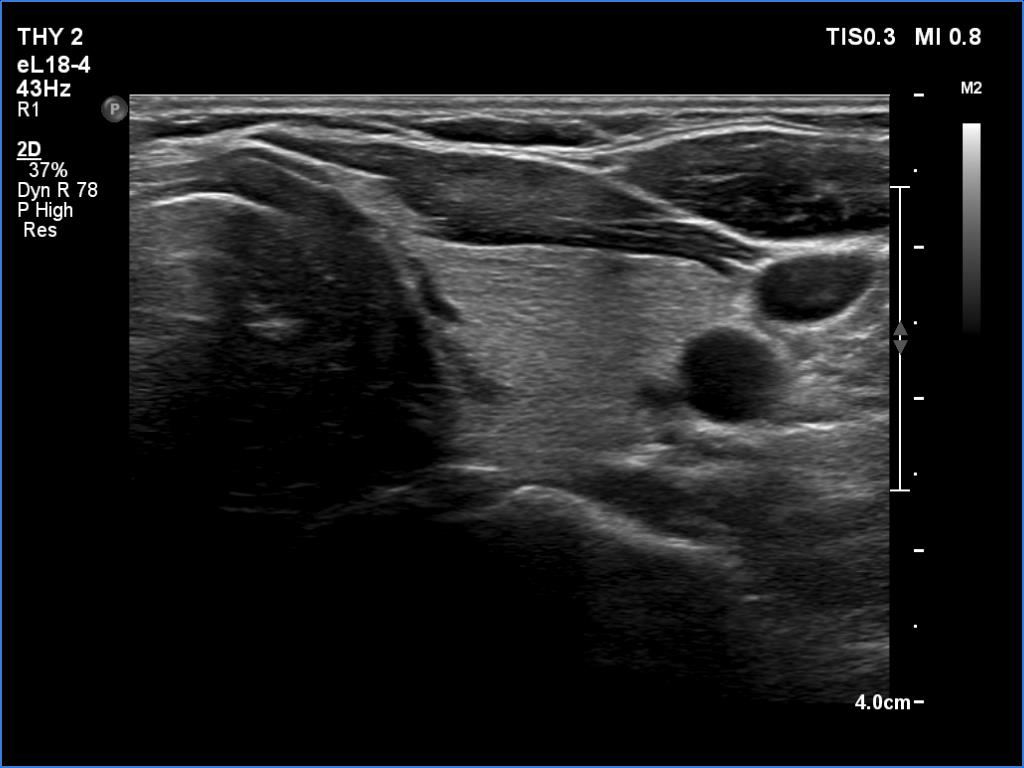

Follow-up 2 months after the first visit (3rd row of images):

Clinical presentation: Within 24 hours of the administration of 32 mg methylprednisolone, the neck complaints and subfebrility had stopped. When the patient reduced the dose to 8 mg daily for 2 weeks as suggested, the left lobe became sensitive. This tenderness has now been significantly reduced, but still persisted at times.

Palpation: The left lobe was tender on palpation.

Laboratory tests: TSH 1.62 mIU/L, FT4 9.97 pM/L, CRP 0.1 mg/L.

Ultrasonography: The right lobe decreased in size as did the extent of hypoechogenic areas in this lobe. The left lobe remained unchanged.

Suggestion: Discontinuation of steroid therapy. TSH in three months.